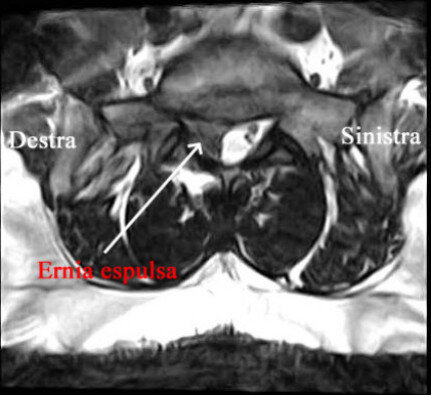

Una risonanza lombare evidenziava un’ernia discale molto voluminosa espulsa L5-S1 sinistra.

Non presentava disturbi di forza all’esame neurologico obbiettivo.

Il paziente non era incline al trattamento neurochirurgico e si optava per ozonoterapia.

Nel corso delle sedute (effettuate alcune con tecnica ecoguidata iuxtaradicolare L5-S1 ed altre paravertebrali) graduale regressione del mal di schiena e diminuzione el dolore sciatico.

Alla fine delle 6 sedute (3 settimane di trattamento), regressione completa del dolore allagamba sinistra, con possibilità di ripresa dell’attività lavorativa.